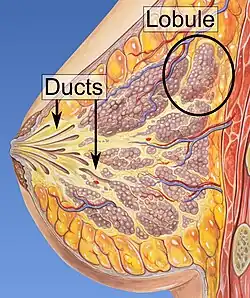

- Histopathology. Although breast cancer has many different histologies, the considerable majority of breast cancers are derived from the epithelium lining the ducts or lobules, and are classified as mammary ductal carcinoma. Carcinoma in situ is proliferation of cancer cells within the epithelial tissue without invasion of the surrounding tissue. In contrast, invasive carcinoma invades the surrounding tissue.[3] Perineural and/or lymphovascular space invasion is usually considered as part of the histological description of a breast cancer, and when present may be associated with more aggressive disease.